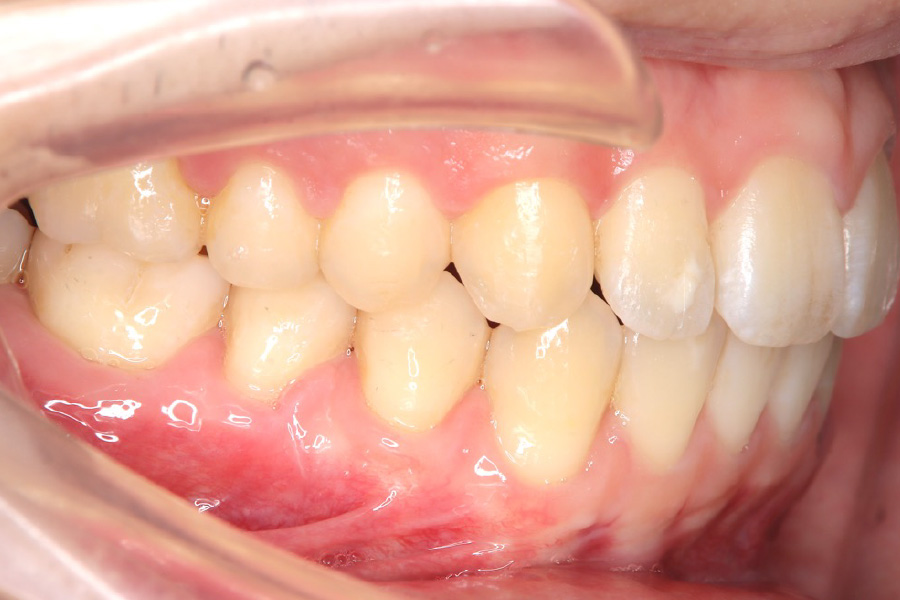

治療後

主訴 歯のガタつき

期間 1年半

治療内容 インビザライン矯正

非抜歯

治療に伴うリスク 矯正終了後は、リテーナーを指示通りに使用し、歯の後戻りを防ぐ必要があります。